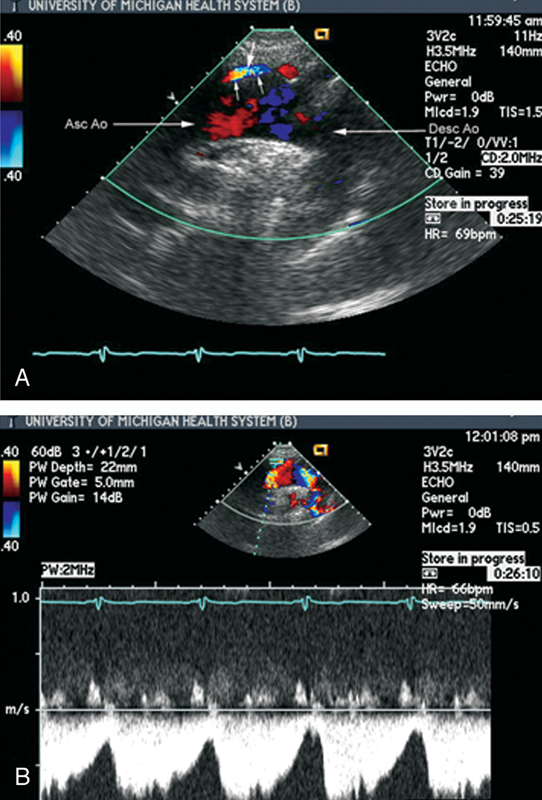

فحوصات تشخيصية لبعض امراض القلب والشرايين التاجية